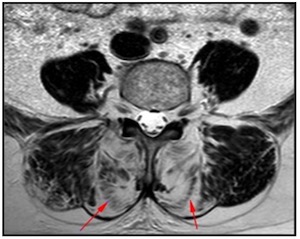

Die tiefliegenden Rückenmuskeln, oftmals auch als autochthon („ortsständig“) bezeichnet, haben eine Schlüsselfunktion bei der Aufrichtung und Stabilisierung der Wirbelsäule [Wagner et al., 2005]. Vor allem die Muskeln des sogenannten „medialen Stranges“ sind segmental angeordnet und daher für die segmentale Stabilisierung und Hauptkontrolle der Wirbelsäule verantwortlich (siehe Abb. 1) [Creze et al., 2015; Deng et al. 2015]. Unterstützt werden diese Muskeln von einem komplexen System aus Faszien. Gut trainierte Muskeln erhöhen diese fasziale Spannung und gewährleisten eine systemische Stabilität [Willard et al., 2012].

Abb.2: Segmental angeordnete autochthone Rückenmuskeln